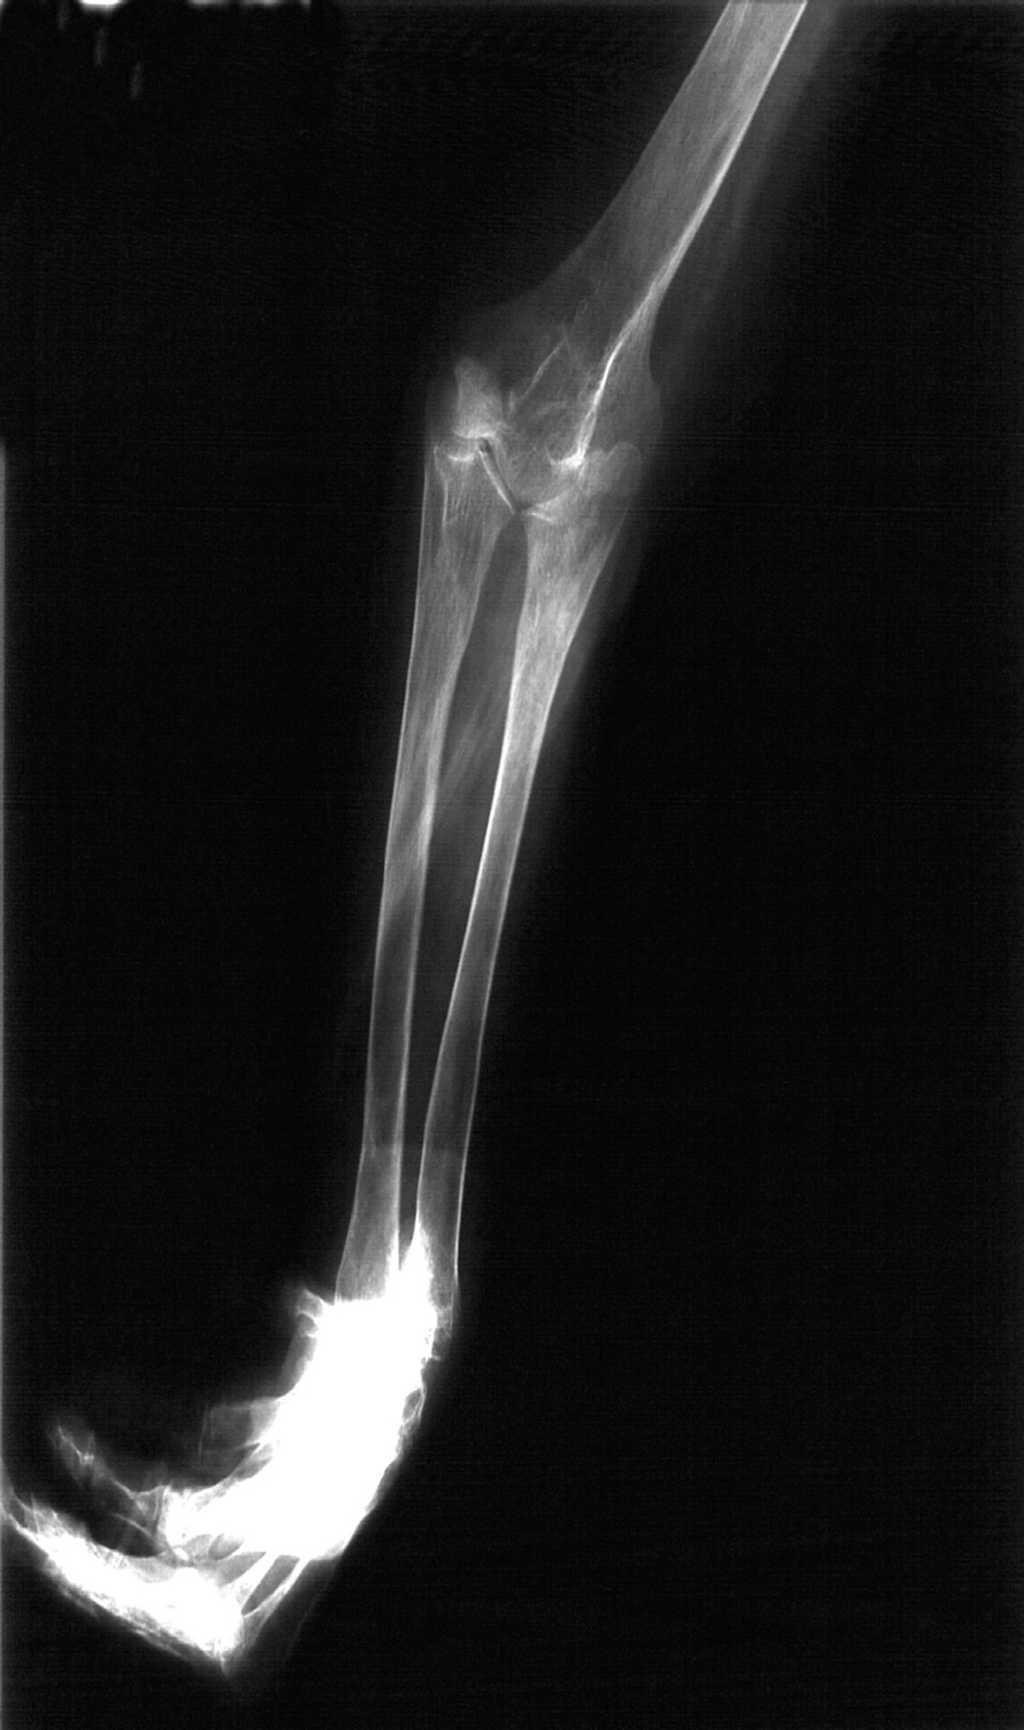

Figura 5. Radiografía anteroposterior del antebrazo. Se observa gran similitud morfológica de los dos huesos en su región proximal, más cercana a la del cúbito, con ausencia de articulación radiocubital proximal.

En el presente caso, en la muñeca, los dos huesos del antebrazo presentan una morfología distinta, lo que hace dudar que sea una duplicación del cúbito. Sin embargo, en el codo se observan dos huesos de morfología más parecida que semejan más a un cúbito, en ambos casos, que a un radio. En la práctica totalidad de las imágenes publicadas se observan casos de niños por lo que, en realidad, no conocemos el aspecto final de los huesos del antebrazo al finalizar el crecimiento, circunstancia que se puede ver en esta paciente. La falta de simetría completa de los huesos del antebrazo no permite hablar de dimelia cubital, aunque la morfología de los dos huesos se acerca más a la del cúbito que a la del radio.